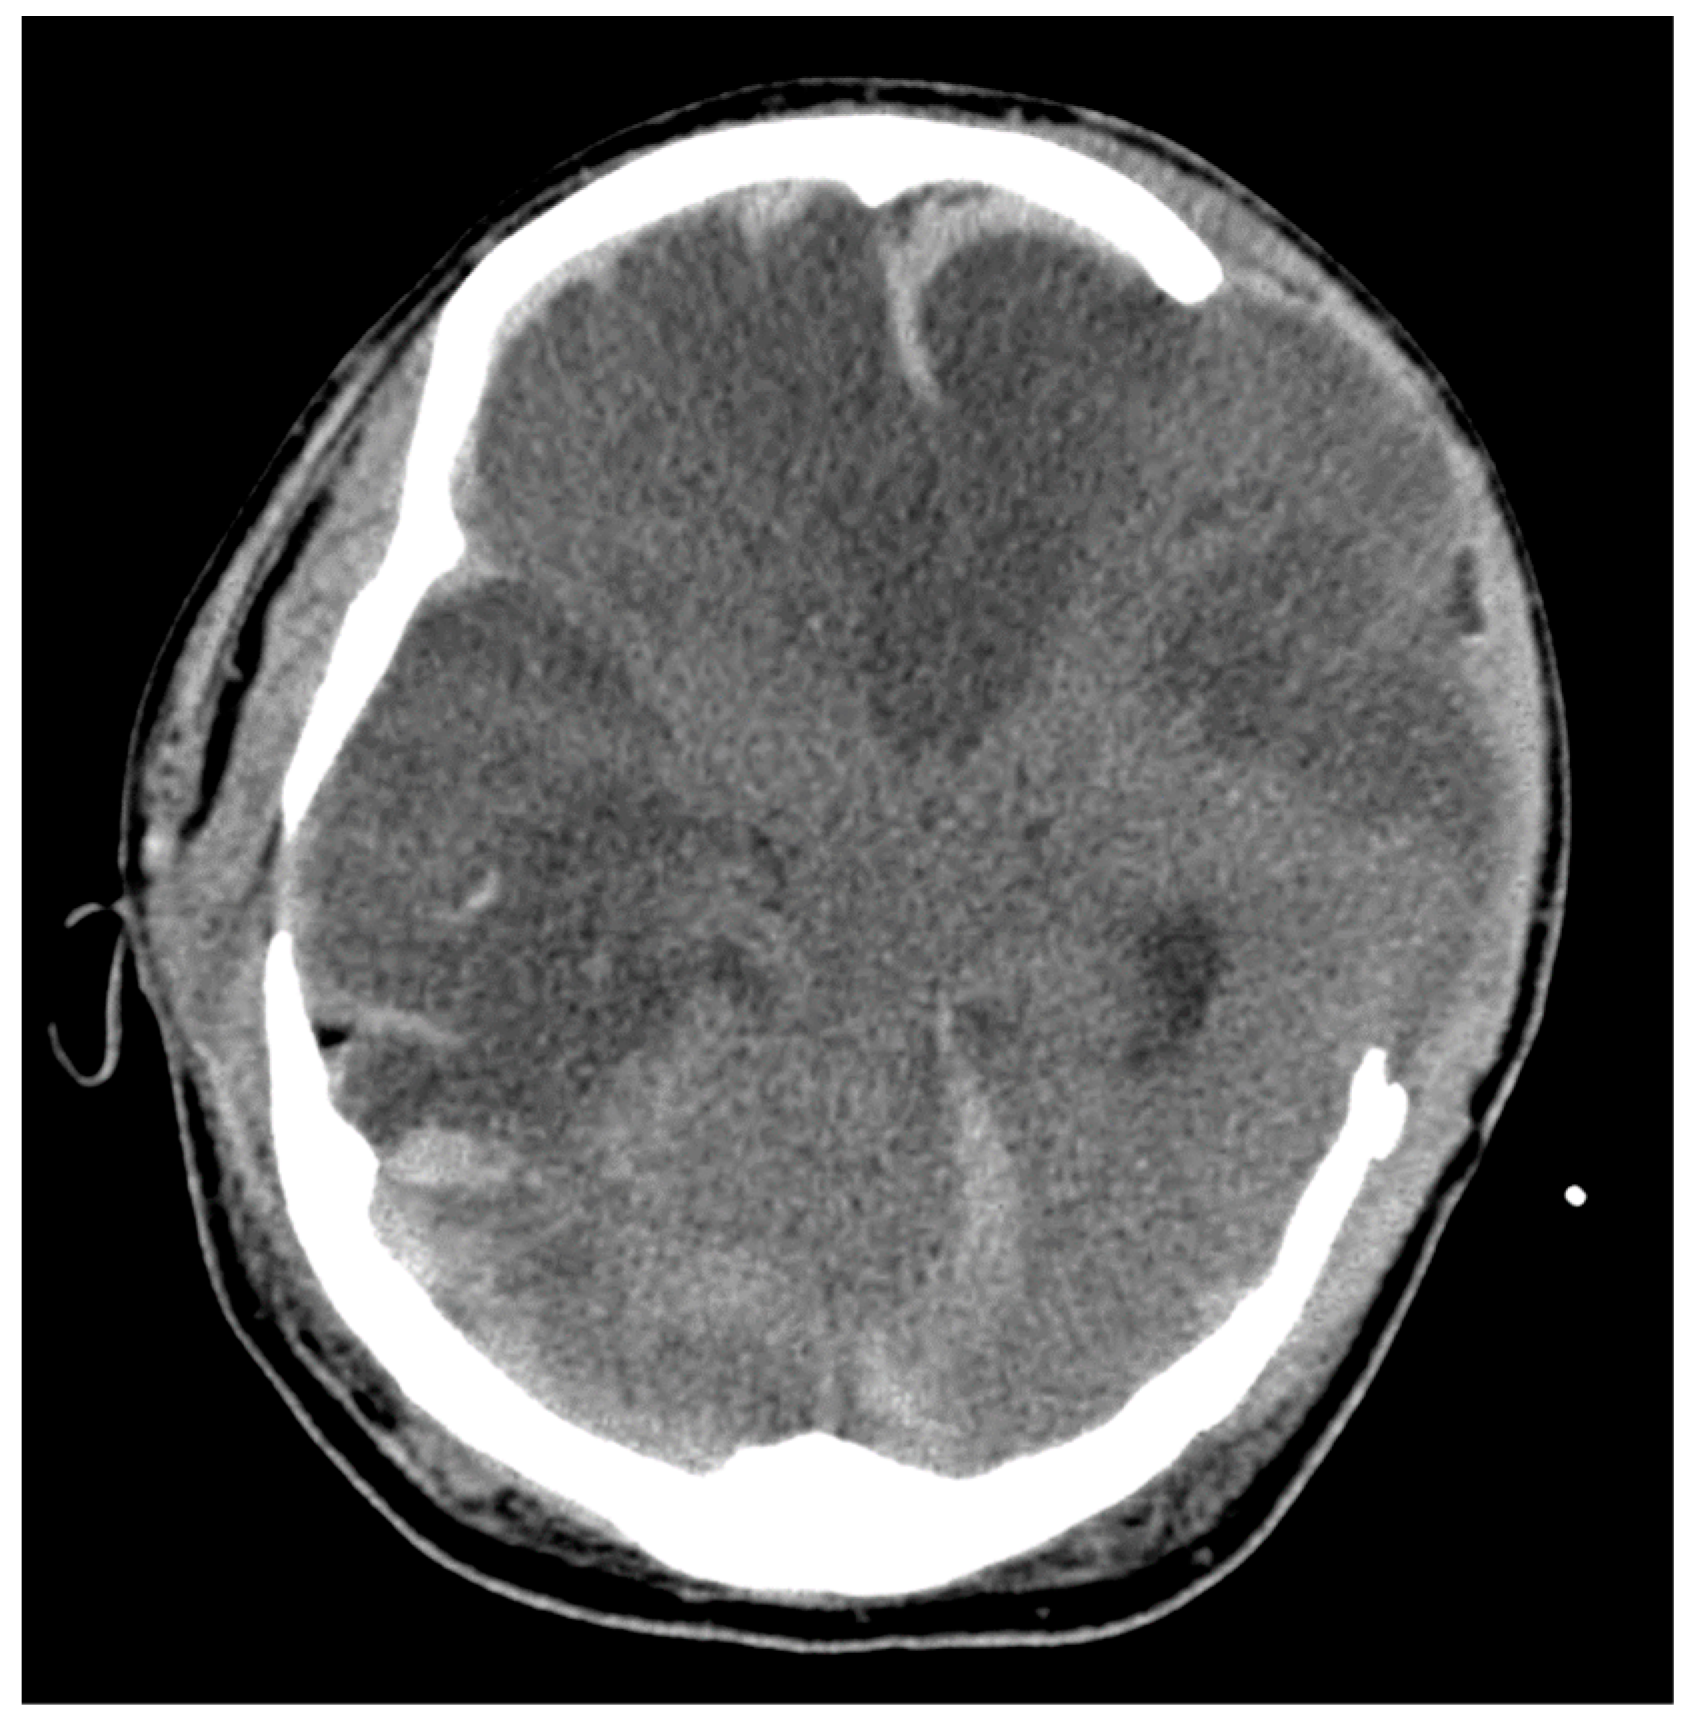

3.2. CT and MRI Neuroimaging Modalities

3.3. Vessel Imaging